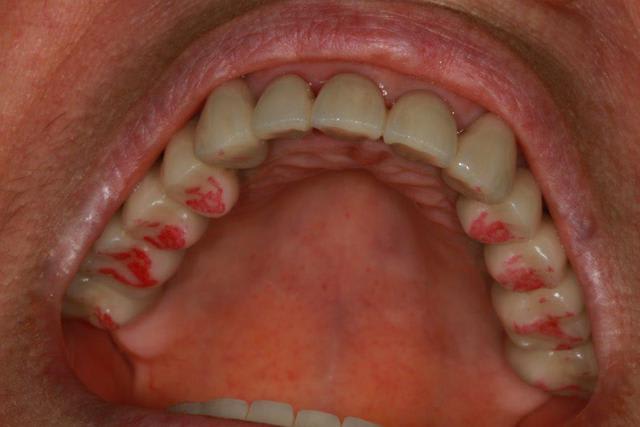

Enlaye, j'ai fait un contrôle avec papier rouge (épais)

ton avis?

Photo 1 dents serrées occlusion sans glissement

Photo 2 le bas après papier rouge

Photo 3 le haut après papier rouge

Photo 4 le bas après retouche et papier rouge

Photo 5 le haut après retouche et papier rouge

Photo 6 latéralité gauche

Photo 7 latéralité droite

La sensation de "rigidité" pour le maxillaire sup s’estompe, la patiente s'approprie ses nouvelles prothèses.

le petit "truc" concernant l'implant semble fonctionner...à merveille.